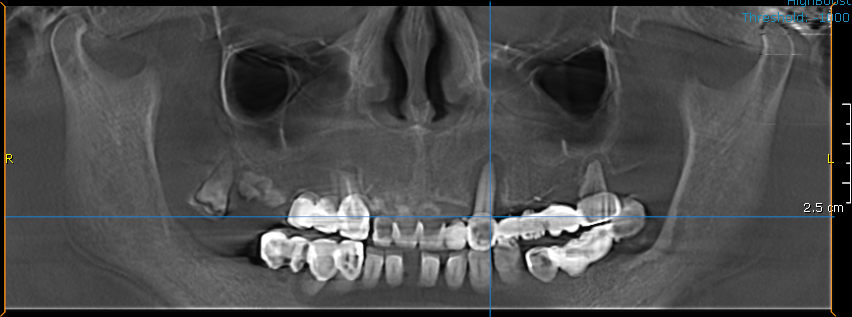

Pacientul a venit la noi cu boala parodontala avansata, care a dus la pierderea dintilor si afectarea structurii osoase.

- Consultul inițial – Am discutat despre dorințele pacientului și am făcut o evaluare completă a sănătății orale.

- Am extras dinții irecuperabili.